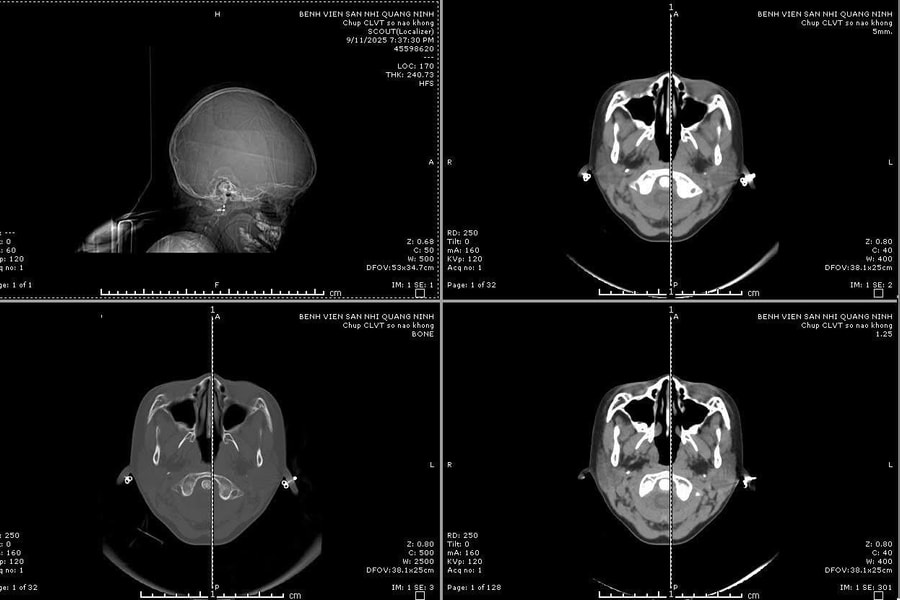

Kích hoạt "báo động đỏ" cứu sống bệnh nhi vỡ sọ phức tạp

Bé gái 6 tuổi nhập viện trong tình trạng hôn mê do tai nạn sinh hoạt, đã được phẫu thuật cấp cứu và hiện sức khỏe ổn định.